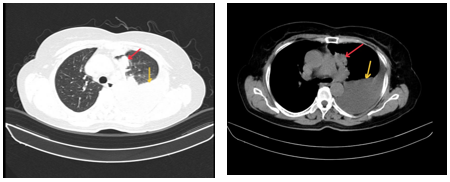

-         Cộng hưởng từ sọ não: Nhu mô bán cầu tiểu não trái và thuỳ đỉnh trái cạnh thể trai có tổn thương tăng tín hiệu trên FLAIR, ngấm thuốc viền sau tiêm, phù não rộng xung quanh, kích thước 11x12mm và 7mm (theo dõi thứ phát). Nhu mô chất trắng cạnh não thất bên và trung tâm bán bầu dục hai bên có vài nốt thoái hoá myelin chất trắng, đường kính <5mm

Hình 2: Cộng hưởng từ sọ não lúc mới nhập viện: Tổn thương tăng tín hiệu trên FLAIR tại bán cầu tiểu não trái và thùy đỉnh trái cạnh não thất (mũi tên đỏ).

-         Chụp MRI sọ não có tiêm thuốc cản quang: Hình ảnh thoái hóa myelin quanh não thất bên và trung tâm bán bầu dục hai bên. Dày nhẹ niêm mạc xoang sàng hai bên. Hiện không thấy nốt ngấm thuốc bất thường nhu mô não.

Hình 4: MRI sọ não sau tiêm thuốc cho thấy các ổ thoái hóa myelin rải rác vùng chất trắng, không ghi nhận tổn thương ngấm thuốc bất thường nhu mô não.